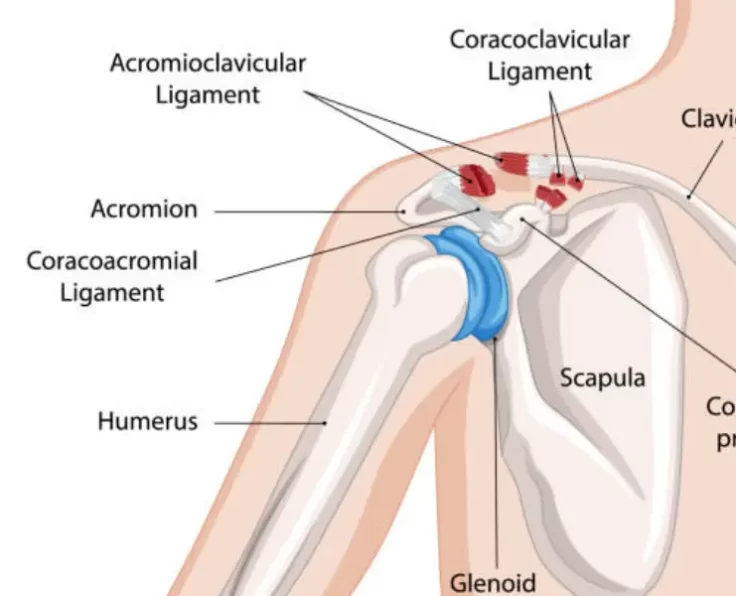

AC Joint Reconstruction

The acromioclavicular joint, often known as the AC joint, is positioned on the top of the shoulder, where the clavicle (collarbone) meets the acromion (shoulder…

AC Joint Excision

The goal of the procedure is to remove the uncomfortable and injured Acromioclavicular Joint (ACJ) without causing it to become unstable.

AC Joint Dislocation

The shoulder is the most mobile joint in the body, it requires a complex system of structures to keep it stable during movement.